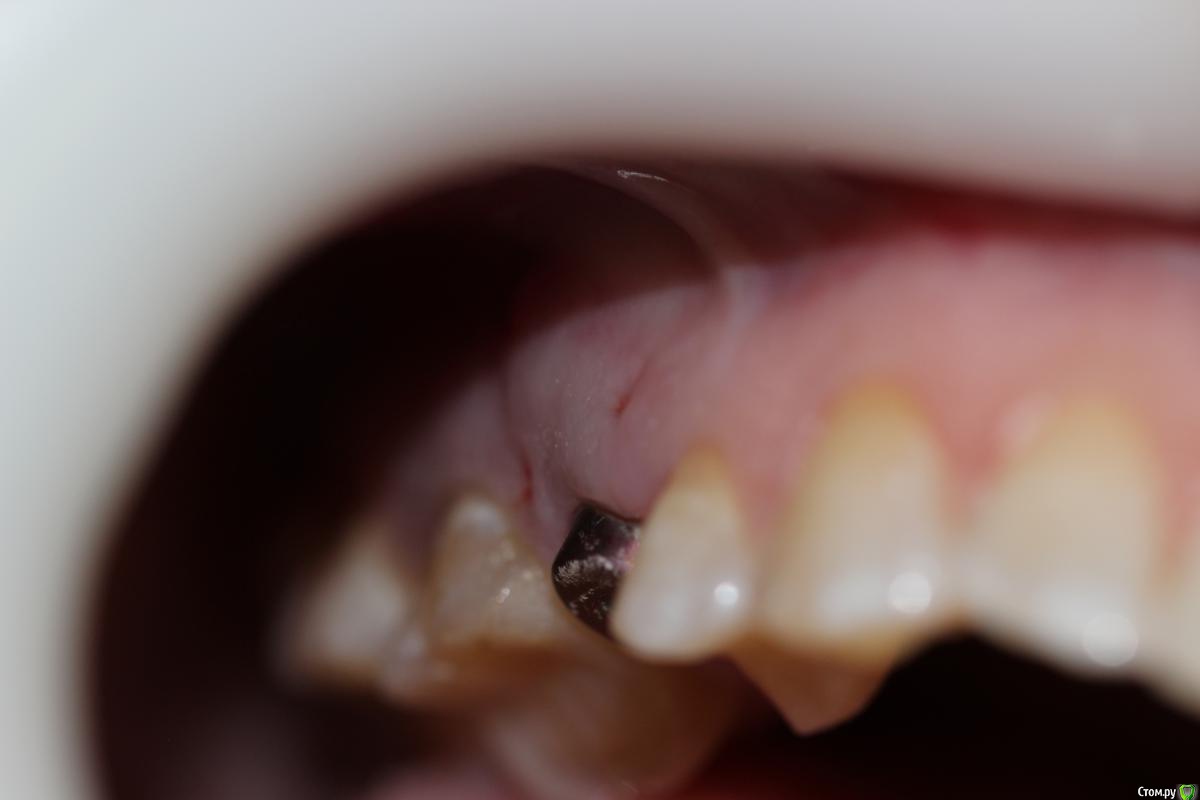

Dr. Khurtsilava Опубликовано 25 октября, 2015 Поделиться Опубликовано 25 октября, 2015 Пациентка обратилась в клинику с жалобами на отсутствие коронки на имплантате 15 в течение года (ставила в другой клинике, клиника закрылась, «голый» Nobel CC остался во рту); наличие дефекта с щечной стороны.Объективно, с щечной стороны обнаруживается дефект альвеолярного гребня в/ч в области имплантата 15 в вестибулярно-язычном направлении; отсутствие коронки на имплантате 15.Манипуляции:1 – забор ССТ с неба конвертной методикой по Зуккелли (спасибо «Доктуру» за это).2 – ушивание непрерывным замыкающим швом Prolene 5-0; лоскут обезжирен – отдыхает в физ. р-ре.3 – в области имплантата внитрибороздковый разрез, ослоение, мобилизация лоскута, деэпителизация сосочков, установка Формирователя Десны, подшивание ССТ, фиксация, ушивание лоскута в области сосочков двойным петлевым швом Prolene 5-0.Рекомендации: гигиена полости рта, мягкая зубная щетка CuraProx 5460, полоскание Curasept 0,2%, солкосерил дентальная адгезивная паста в донорской зоне и зоне реципиента, найз 2т 2р/д утром и вечером 4 дня.На 7 сутки снятие швов, соблюдение рекомендаций.Пациентка по семейным обстоятельствам пропала на пол года, явилась вчера на продолжение лечения.Вот такой вот приятный десневой рекол с врем коронкой) 10 Ссылка на комментарий